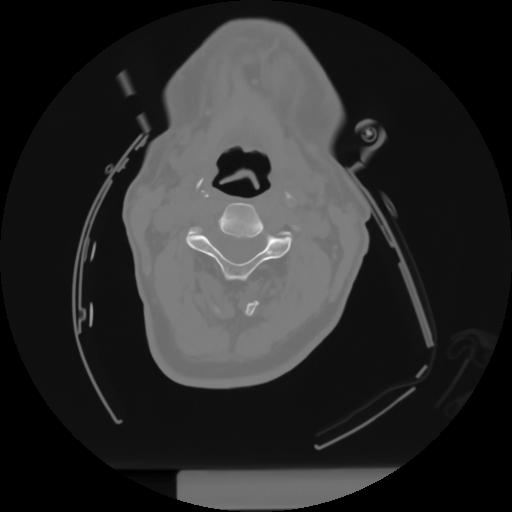

10 P.BLANDAS,,Axial,2.0,P.BLANDAS,,